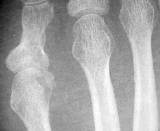

Intensity inhomogeneities often occur in real-world images mainly due to different spatial lighting and deficiencies of imaging devices. For example in MRI, imperfections in the radio-frequency coils or problems associated with acquisition sequences cause intensity changes. The motivation for this paper was the task of segmenting 3D images stemming from focused ion beam (FIB) tomography. While classical -ray tomography does often not reach the required material resolution, FIB tomography enables to investigate the 3D morphology of structures on a scale down to several nanometers. The material is successively removed by a focused ion beam and after every section, the surface is displayed by scanning electron microscopy. Several hundred of these serial slices finally form a 3D image. A typical slice of a 3D FIB tomography of aluminum with silicon carbide (SiC) particles (larger black parts) and copper aggregations (small white parts) is shown in Fig. 1(a). The segmentation has to distinguish between the particles, the aggregates and the surrounding aluminum matrix. However, due to the intensity inhomogeneities, a segmentation based on the gray-values gives a very bad result. Fig. 1(b) and 1(c) show segmentation results for a 3D FIB data set using a supervised gray-value based segmentation method without considering the illumination. Therefore, we have to choose one cluster center for each of the three classes, i.e., in total three gray-values that are close to the classes aluminum, SiC and copper, respectively. Unfortunately, the cluster centers cannot be chosen appropriate for all parts of the image so that either too many or not enough particles are detected. Therefore the segmentation of such images has to take the intensity inhomogeneities into account.

The first row shows results for an X-ray image of bones. The result of our model is compared to the result of M1) with the parameters proposed in the paper [26], i.e., and . The white part corresponds to positive values of the resulting function of the level set method M1). Furthermore, we depict the result of the two-step method M3) to show that correcting the illumination only in the preprocessing step before the segmentation is not sufficient. The methods M1) and M3) perform equally well, where each one shows different slight artifacts. The proposed model gives the best segmentation result, in particular the left bone and the upper part of the right bone are segmented correctly.